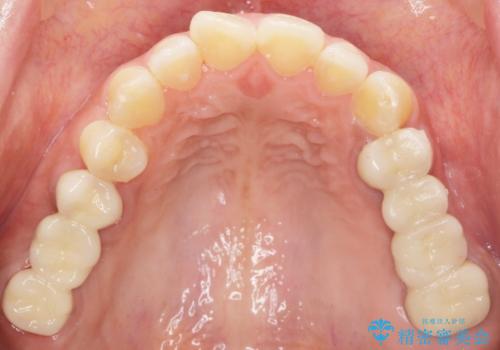

使っていない親知らず(右上8)を右上7抜歯窩に移植し、支台歯としてブリッジによる補綴治療を行いました。

インプラントや入れ歯を使わずに奥歯でしっかり咬むことができるようになり、また見た目も自然だと大変喜んで頂けました。

クラウンの種類:メタルボンドクラウン エコノミー フルベイク